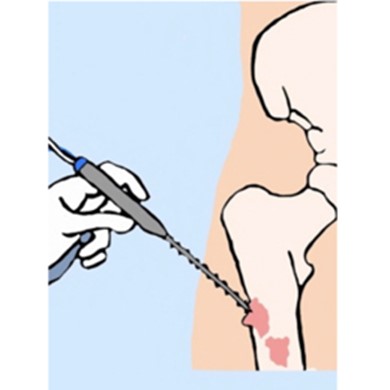

An incision is made that extends from the biceps femoris muscle over the knee joint and goes down the fibula bone to the ankle. The skin surrounding the previous biopsy site is left intact.

Dissection

Separating all major arteries, veins, and nerves from the tumor. In rare cases a nerve (s) may need to be removed if it is involved by the bone sarcoma. For this procedure it is important to properly identify the popliteal, tibial, and peroneal arteries and veins as well as the tibial nerve. Once the blood vessels and nerves are separated, they can be retracted (moved away from the tumor) and protected throughout the procedure.